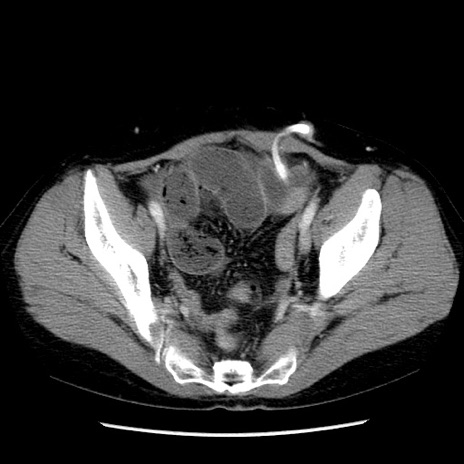

症例6(横断像)

【症例】50歳代女性

【主訴】下腹部痛

【現病歴】本日朝より下痢2回あり。 昼食を食べた後、嘔吐3回、下腹部痛認め、症状軽快せず、当院救急搬送。

最終食事:本日昼(生ものなし)。 昨日の夜、刺身を食ぺたとのこと。周囲に同様の症状の者なし。普段、排便は毎日あるとのこと。

【既往歴】卵巣癌術後(8年前に当院で卵巣摘出)

【身体所見】 意識清明、腹部:平坦、腸蠕動音→、やや硬、下腹部自発痛・圧痛あり、反跳痛あり、筋性防御なし。

【データ】WBC 16000、CRP 0.01